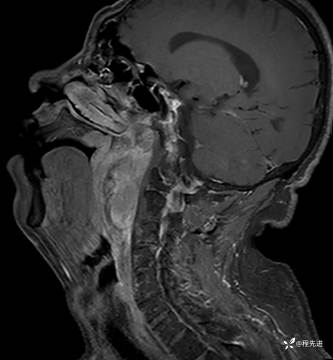

【面颈】特别精彩病例|呼吸费力3月余,声嘶2月余,左侧鼻咽部占位期待您的精彩解读

患者性别:男

患者年龄:58岁

主诉:呼吸费力3月余,声嘶2月余

现病史:患者3月前劳作后出现呼吸费力,胸闷气促。外院颈部CT检查提示:左侧颈部肿物。3月来颈部肿物逐渐增大,劳作后呼吸困难加重;2月前出现声音嘶哑,逐渐加重。现患者至我院门诊就诊,拟“左侧咽旁间隙良性肿瘤”收住入院

MRI平扫+增强:

T1: